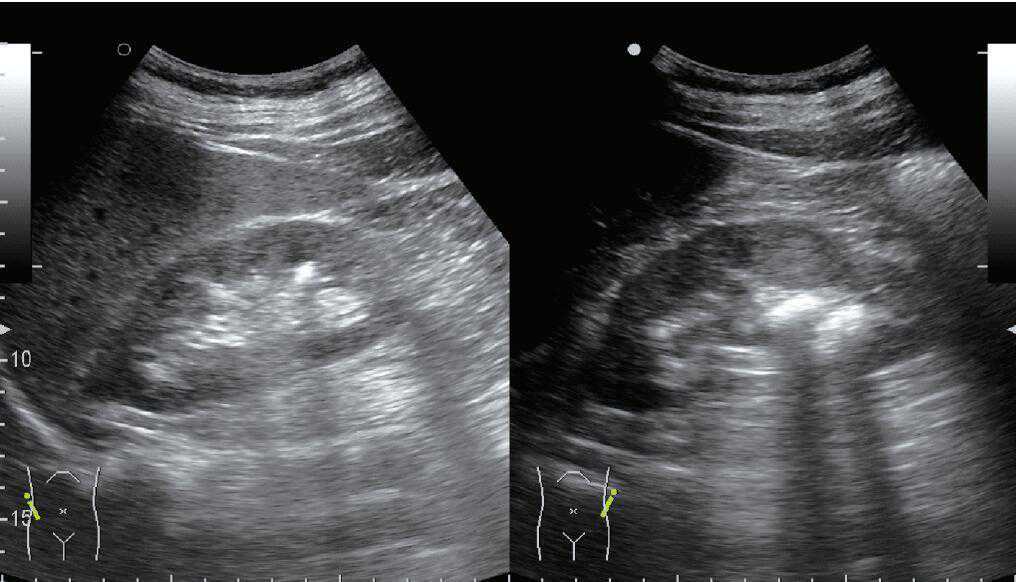

(1)外部混响:超声垂直照射到平整的高反射界面,如胸壁、腹壁,超声波在探头和界面之间来回反射,发生多次反射。混响的形态呈等距离多条回声,回声强度依深度递减(图6)。

图6肺内气体所致的外部混响伪像(箭头示A线)